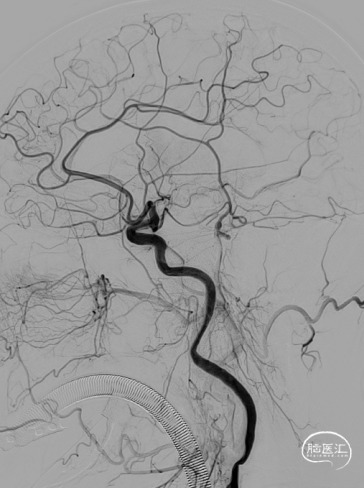

手术过程

路径困难是导致困难取栓的常见原因之一,既往因为普通导引导管较硬而无法通过迂曲血管到达目标血管,并增加手术时间。同时既往中间导管通过性能差而无法顺畅的实现高到位并进行抽吸,两者大大降低了取栓效率。普微森MidAccess™导引导管 088-90 cm具有8F普通导引导管直径,通过性能明显优于普通导引导管,特别是在该病例RCCA如此迂曲的情况下,仅在泥鳅导丝引导下就可以顺利通过Z字型迂曲到达C1段,为后续068中间导管提供了有力支撑并缩短的取栓距离。普微森MidAccess™导引导管 068-132 cm具有口径大、高到位、耐疲劳的特点,在微导管微导丝引导下3次顺利通过眼动脉段并送至RMCA起始段及M1中远端进行抽吸,不仅缩短了取栓时间,也避免了反复支架取栓对血管管壁的损伤。